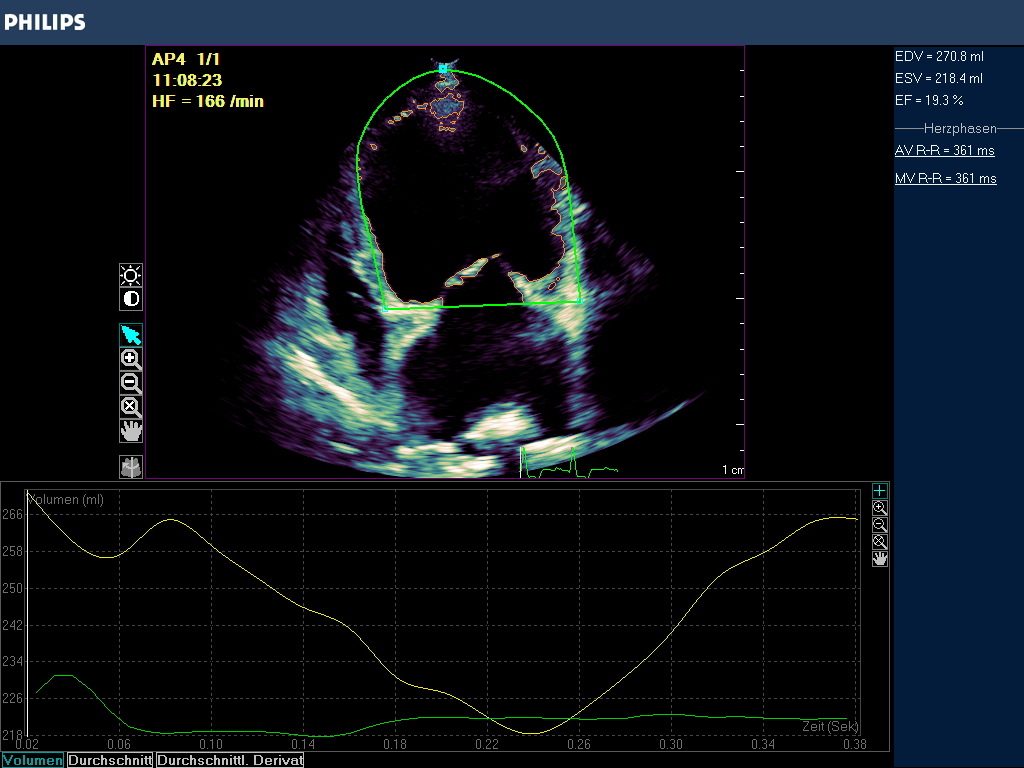

Das Ergebnis der GLS wird in negativ -%- Zahlen angegeben. In besonders schwer erkrankten Fällen kann die Zahl positiv werden! Je höher die negative Zahl angegeben wird desto stärker ist die Verformung bzw. Kinesie des Muskels. Darüber hinaus wird nach der Simpson Methode eine Ejektionsfraktion ermittelt , die in EF % angegeben wird (Abb. 3).

Globale Dysfunktion des linken Ventrikels durch Dilatation bei einer DKM oder infolge eines Ductus botalli persisitens oder einer chronischen Aorteninsuffizienz können bei hochgradigen Befunden sehr niedrige oder gar positive Strainzahlen hervorbringen. Die Ejektionsfraktion ist in diesen Fällen i.d.R. vermindert (Abb. 3).